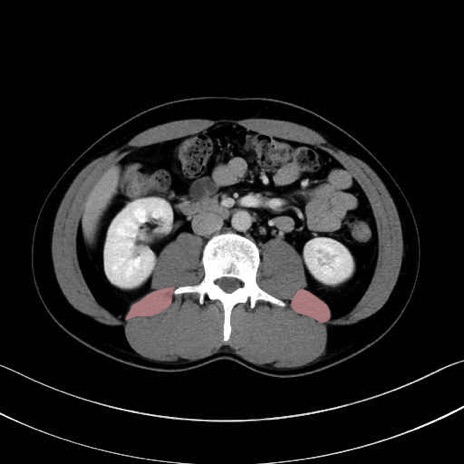

腰方形筋(quadratus lumborum muscle)のCT画像の解剖

腰方形筋 (Quadratus lumborum)